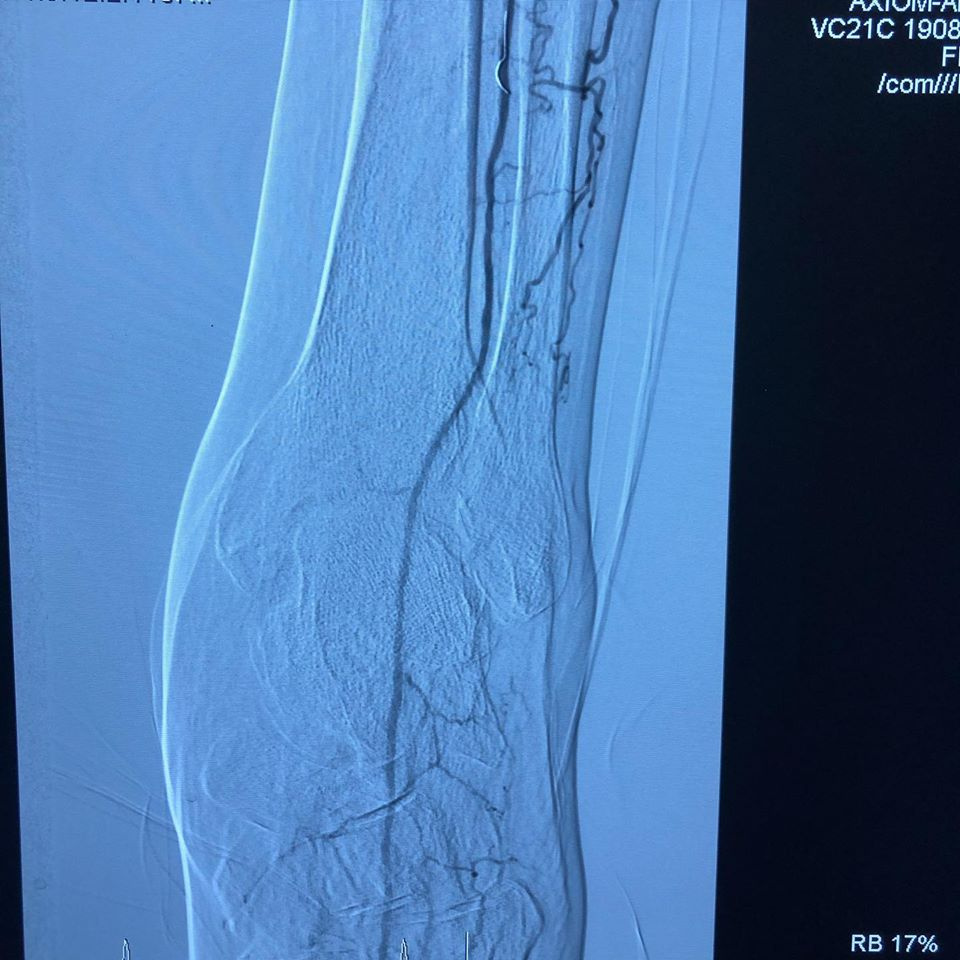

Se pasa a Hemodinamia donde se observa lesiones estenoticas en arteria poplitea y sin vasos tibiales, recanalizando en arteria pedía

(FP2, IP4, P2 GLASS 3) y se realiza angioplastia poplitea y de tibial anterior, mejorando el flujo distal, se realiza amputacion de falange distal del dedo y se observa buena evolución 24 hrs después sin complicaciones con alta a su domicilio